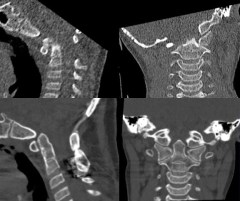

- réduire la luxation par traction (étrier de gardner ou halo)

- fixer par arthrodèse postérieure

- C1-C2 si instabilité limitée

- occipito-cervicale si grande instabilité intéressant C0-C1

réduction et consolidation après arthrodèse postérieure maintenir une immobilisation par minerve ou halo jusqu’à consolidation osseuse ; les trisomique ont souvent une ostéoporose qui compromet la consolidation.les techniques de fusion cranio-cervicales sont détaillées sur la page fusion crânio-cervicale